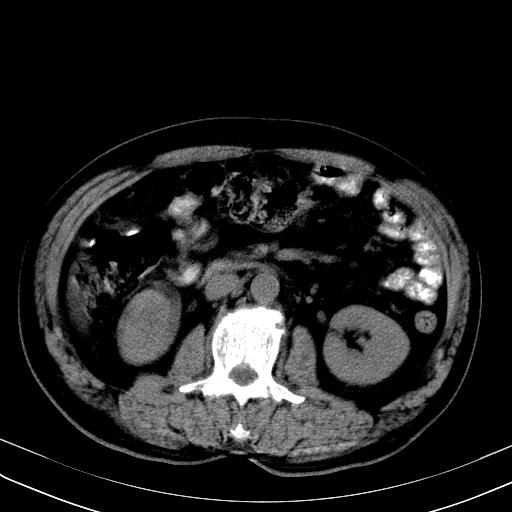

先行ct平扫,纵膈内多发软组织影,ct值约为36hu,以下为增强扫描和腹部平扫。

经典?纵膈多发肿大淋巴结。腹膜后未见异常。

还见胃窦壁增厚!转移亦有可能!

1)考虑淋巴瘤。2)双侧少量胸腔积液。

多发肿大淋巴结影,肝内改变需结合强化观察

多发肿大淋巴结影,肝内改变需结合强化观察。